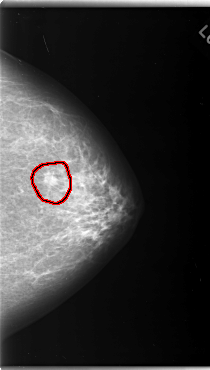

C_0124_1.LEFT_CC

FILE: C_0124_1.LEFT_CC.OVERLAY

TOTAL_ABNORMALITIES 1

ABNORMALITY 1

LESION_TYPE MASS SHAPE OVAL MARGINS SPICULATED

ASSESSMENT 5

SUBTLETY 5

PATHOLOGY MALIGNANT

TOTAL_OUTLINES 1

BOUNDARY